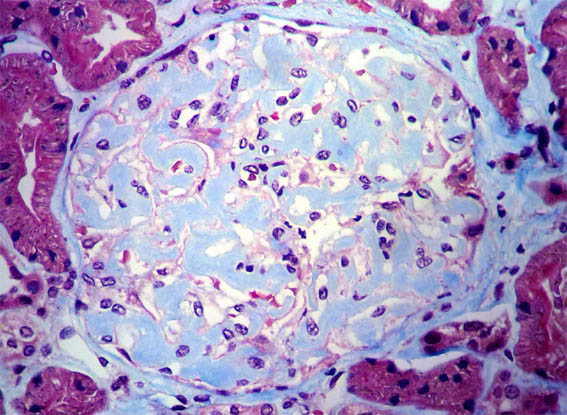

Figure 2.

H&E, X400.